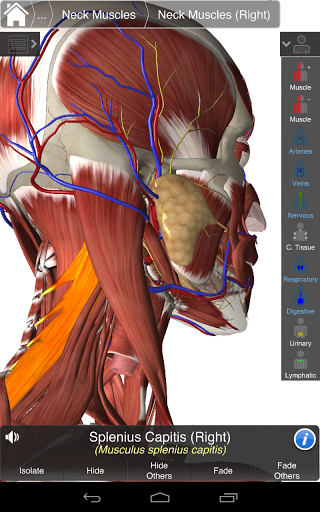

Essential Anatomy 3 reprezentuje najnowsze przełomowe technologie 3D i innowacyjny design. Najnowocześniejszy silnik graficzny 3D, zbudowany na zamówienie przez 3D4Medical od podstaw, zapewnia bardzo dokładny model anatomiczny i zapewnia doskonałą jakość grafiki, której żaden inny konkurent nie jest w stanie osiągnąć.

Aplikacja przedstawia unikalne podejście do uczenia się ogólnej anatomii. Grafika jest nieporównywalna i sprawia, że uczenie się, dzięki wykorzystaniu treści informacyjnej i innowacyjnych funkcji, jest bogatym i wciągającym doświadczeniem.

NOWA TECHNOLOGIA 3D

Essential Anatomy 3 jest responsywny, wizualnie oszałamiający i pozbawiony wysiłku. Aplikacja jest w pełni 3D, co oznacza, że możesz zobaczyć dowolną strukturę anatomiczną w izolacji, a także pod dowolnym kątem.

Mądra funkcjonalność znajdująca się w aplikacji pozwala użytkownikowi usunąć warstwy mięśni za pomocą narzędzia "skalpela". Ta aplikacja zapewnia użytkownikom możliwość włączania / wyłączania systemów bez potrzeby wyłączania poszczególnych struktur lub pomieszania wielu predefiniowanych kart regionalnych, tak jak w przypadku innych aplikacji.

Essential Anatomy 3 został zaprojektowany z myślą o użytkowniku - samo ciało staje się interfejsem. W odróżnieniu od innych aplikacji 3D, które opierają się na wcześniej zdefiniowanych układach anatomicznych i regionalnych rozbiorach, które kierują użytkownikiem, Essential Anatomy 3 3D4Medical pozwala znaleźć to, czego szukasz bez komplikacji.

---- Ponad 4000 bardzo szczegółowych struktur anatomicznych

---- Tryb wielokrotnego wyboru - Ukryj / Zniknij / Izoluj pojedyncze lub wiele struktur

---- Prawidłowa wymowa audio dla każdej struktury

---- nomenklatura łacińska dla każdej struktury anatomicznej